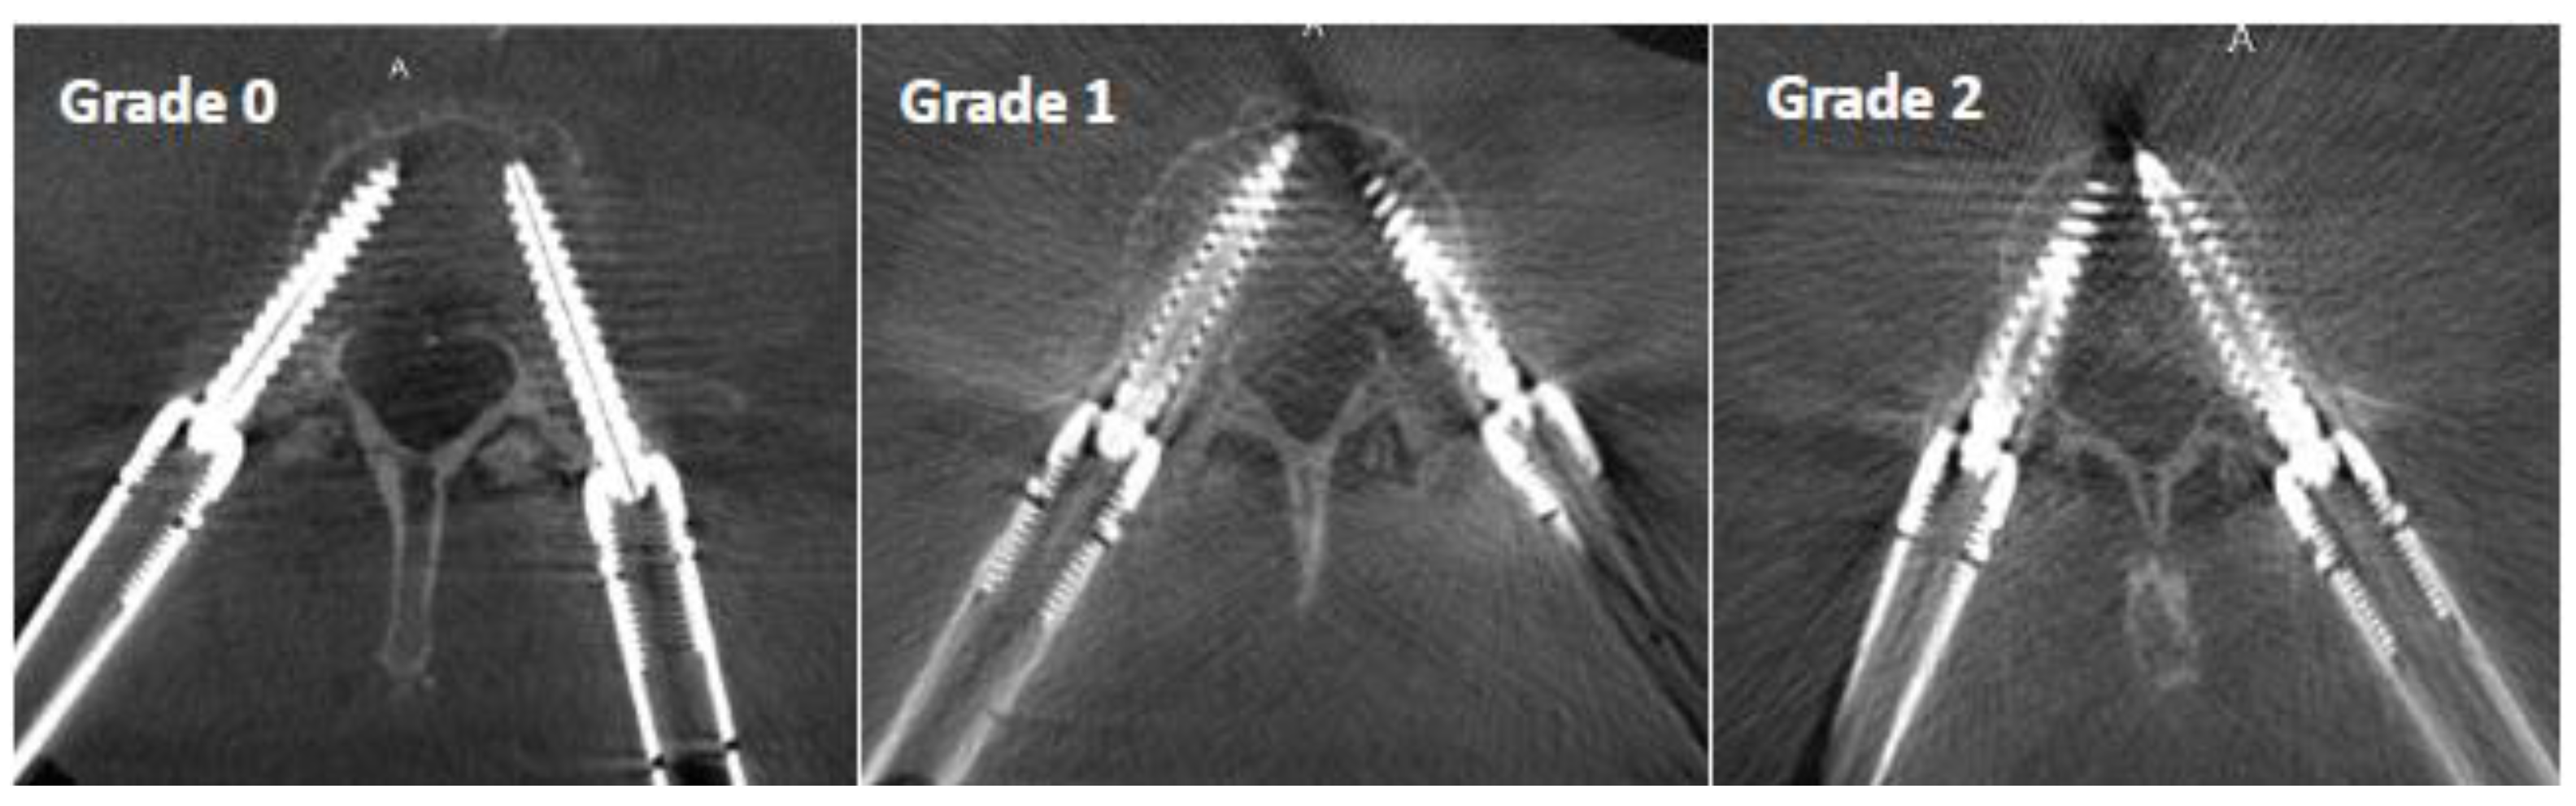

The perception of image clarity around the screw contours was rated using an image quality scale based on the following criteria (Figure 4):

Figure 4.

Pedicle screw metal artifact quality scale: Grade 0 represents a clearcut image of the screw and bony structures, Grade 1 allows assessment of the screw position with some limitations due to artifacts, and Grade 2 has a strong artifact which represents a limitation for the assessment of the exact screw position.

- Grade 0: mild artifact, screw thread clearly visible, cortical bone clearly visible, bone soft tissue interface clearly visible, clear interpretation possible;

- Grade 1: moderate artifact, screw thread visible, cortical bone with unclear portions, bone soft tissue interface distinguishable, interpretation possible;

- Grade 2: strong artifact, screw thread unclear, cortical bone contours unclear, bone soft tissue not distinguishable, interpretation difficult.